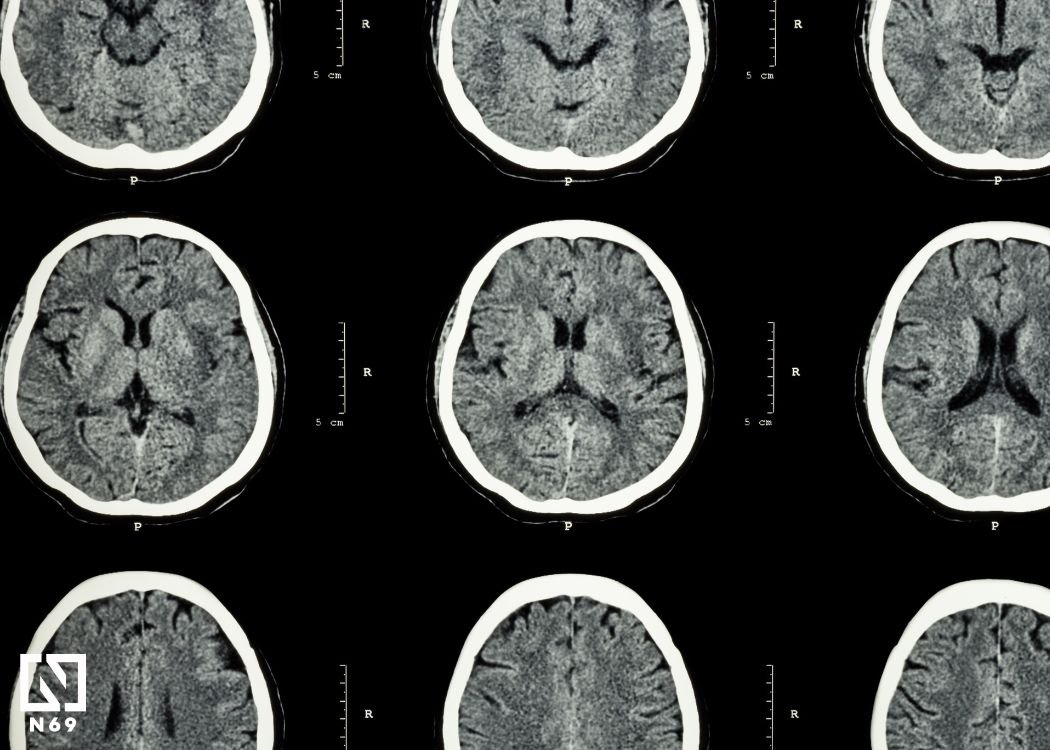

Centralnym tematem książki jest to, co dzieje się z seksualnością, gdy mózg ulega zmianie wskutek choroby, urazu, zabiegu neurochirurgicznego lub procesu neurodegeneracyjnego. Baird opisuje, jak udary, padaczka, demencja, guzy czy urazy głowy mogą diametralnie zmieniać życie intymne: od spadku zainteresowania seksem, przez trudności w odczuwaniu przyjemności, aż po nagłe nasilenie popędu lub pojawienie się zachowań impulsywnych. Pokazuje, że zmiany te nie są rzadkimi wyjątkami, lecz realnym i często pomijanym elementem obrazu klinicznego.

Autorka prowadzi czytelnika przez neurobiologiczne podstawy seksualności wyjaśnia, które obszary mózgu odpowiadają za pożądanie, pobudzenie, więź i kontrolę impulsów, a także jak doświadczenia, relacje i sama aktywność seksualna mogą wpływać na plastyczność mózgu. Dzięki temu książka nie tylko tłumaczy mechanizmy zaburzeń, ale też pokazuje, że relacja między mózgiem a życiem intymnym działa w obie strony: mózg kształtuje zachowania, ale doświadczenia emocjonalne i relacyjne również zmieniają jego funkcjonowanie.

W neuropsychologii, gdy mówi się o „najbardziej zaangażowanych” strukturach mózgu w kontekście popędu i zachowań intymnych, niemal zawsze pojawia się ciało migdałowate - niewielka, ale niezwykle wpływowa struktura układu limbicznego. To właśnie ono odgrywa kluczową rolę w przetwarzaniu emocji, reakcji na bodźce społeczne oraz w nadawaniu znaczenia sygnałom związanym z nagrodą i zagrożeniem. Z tego powodu jego funkcjonowanie silnie łączy się z pożądaniem, pobudzeniem i kontrolą impulsów.

Neuropsychologia pokazuje, że ciało migdałowate działa jak swoisty „filtr emocjonalny” dla bodźców; ocenia ich znaczenie i wpływa na reakcje fizjologiczne oraz zachowanie. Gdy jego aktywność jest prawidłowa, pomaga regulować popęd i dostosowywać zachowania do kontekstu społecznego. Jednak uszkodzenia lub zaburzenia w obrębie płatów skroniowych, gdzie się znajduje, mogą prowadzić do wyraźnych zmian od obniżenia zainteresowania seksem po impulsywność i hiperseksualność.

Z perspektywy neuropsychologii ciało migdałowate nie działa jednak w izolacji. Tworzy sieć z podwzgórzem, korą przedczołową i innymi strukturami układu nagrody. Podczas gdy ono nadaje bodźcom znaczenie emocjonalne, kora przedczołowa pomaga ocenić konsekwencje i hamować impulsy, a podwzgórze reguluje reakcje hormonalne i fizjologiczne. Zachowania intymne są więc efektem współpracy całego układu, a nie pojedynczego „ośrodka”.